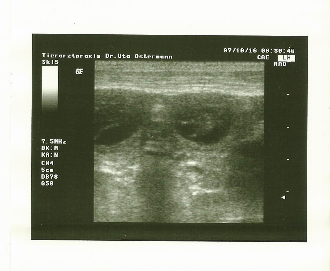

Gestern ging es zum Ultraschall ! Hurra!  Peaches und Anton werden Eltern !!!!

Eigentlich wussten wir es schon vorher, denn Peaches hat lehrbuchmässig alle Anzeichen einer Schwangerschaft gezeigt. Aber es ist so schön, einen ersten Blick auf die Babys werfen zu dürfen.